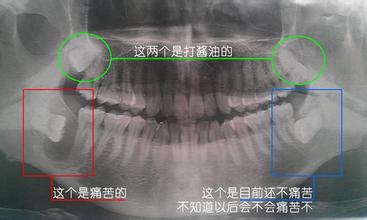

不一定,需要看情況。如果是位置正,有正常咬合關(guan) 係、修複需要可以用作基牙、磨牙缺失較早,考慮第二磨牙前移時,全身原因不宜拔牙、位置低,埋伏深,對鄰牙無影響,沒有發炎等情況,可以先保留觀察智齒,如果出現不良影響則需要拔除。

智齒0-4顆不等,有的人有4顆,有的人有2顆,是否能一次性拔除?這顯然是不行的,一般建議一次拔一顆,或者是同側(ce) 拔牙兩(liang) 顆,這還需要看自身是否能夠承受以及拔牙複雜程度高不高。